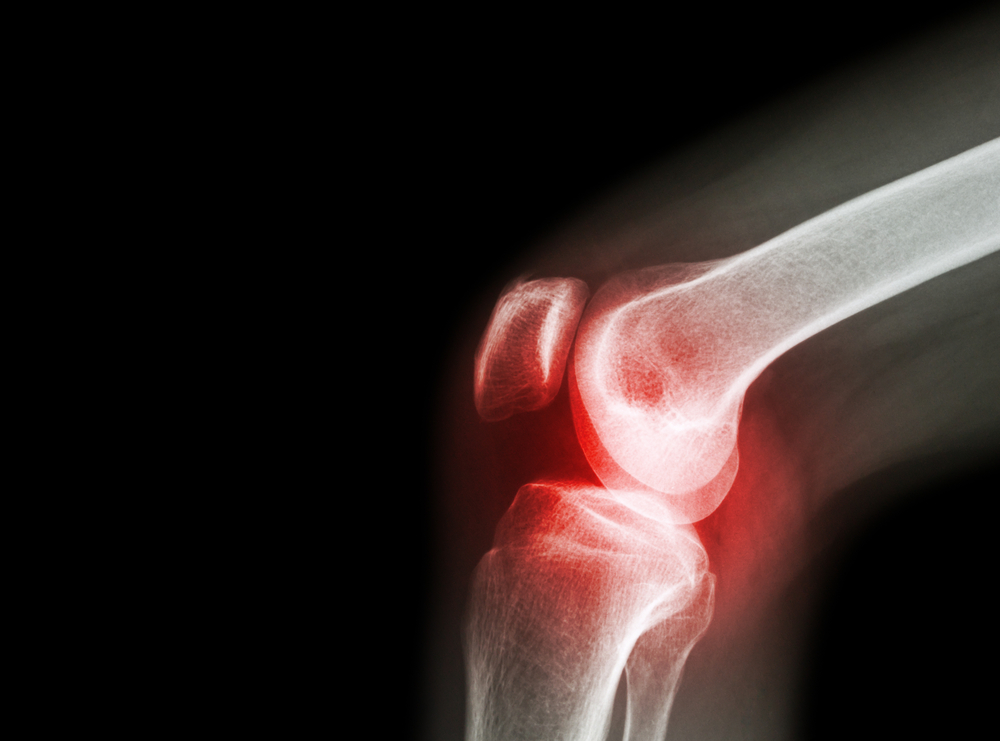

Tratamento e Diagnóstico – O diagnóstico é feito com base em exames clínicos, laboratoriais e de imagem (raios-X e ressonância magnética). É importante lembrar que o diagnóstico e o tratamento devem ser sempre feitos e acompanhados por um médico e, em geral, é necessária a participação do dermatologista e do reumatologista ao longo da jornada do paciente. O tratamento da artrite psoriásica varia de acordo com a forma como a doença se manifesta e pode incluir fisioterapia, medicamentos de uso tópico, anti-inflamatórios e, nos casos mais severos, drogas modificadoras da doença reumática (DMARDs) e cirurgia. A adoção de hábitos saudáveis, como não fumar, praticar exercícios físicos e tomar banhos de sol também são importantes para melhorar a qualidade de vida. Por causa das mudanças que a artrite psoriásica impõe ao paciente, também pode ser necessário procurar apoio psicológico. “A artrite psoriásica pode representar um grande impacto na vida dos pacientes, tornando as atividades rotineiras difíceis de serem executadas, enquanto que os sinais na pele podem provocar problemas sociais e psicológicos”, completa Dr. Célio.